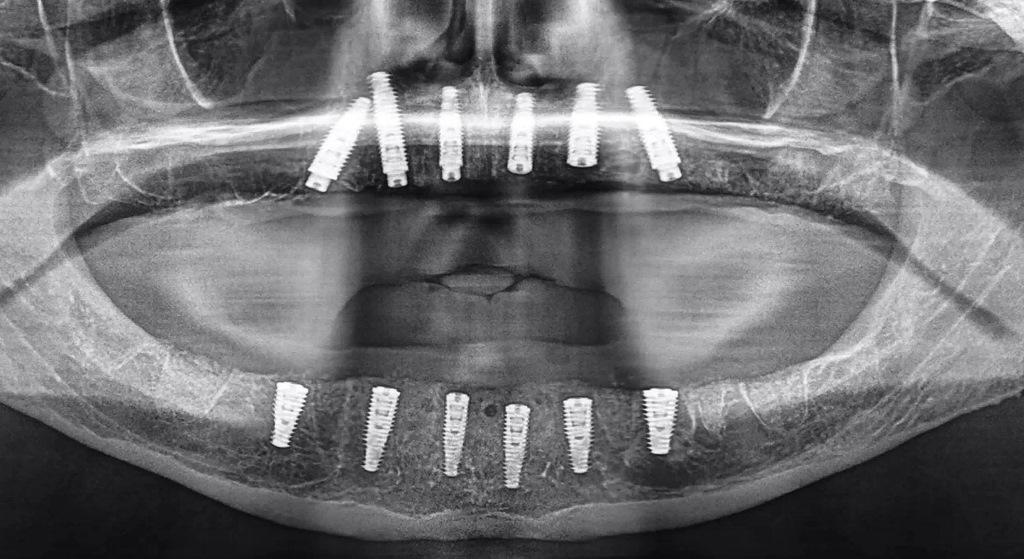

Восстановление кости нижней челюсти было выполнено с использованием пьезоэлектрической хирургии (PIEZOSURGERY, mectron) и набора вращающихся инструментов для хирургического контурирования и модификации альвеолярного отростка (Alveoplasty Surgical Kit (артикул ALV18) Meisinger), чтобы обеспечить достаточную ширину и пространство для реставрации с опорой на имплантат. После завершения редукции кости на альвеолярный отросток нижней челюсти был установлена костная остеотомическая направляющая. Усовершенствованная сегментация, созданная с помощью ИИ, обеспечила плотную посадку направляющей, которая затем была закреплена тремя горизонтальными анкерными штифтами и стабилизаторами направляющей для фиксации направляющей в процессе препарирования (фото 16a). Как только шесть имплантатов были успешно установлены, направляющая была удалена, обнажив уменьшенную кость и лунки после удаления (фото 16b). В углубления после удаления и оставшиеся отверстия было помещено примерно 1 см³ минерализованной кортикальной и губчатой кости. Значения коэффициента стабильности имплантата были недостаточны для немедленной нагрузки, и поэтому для имплантации дуги нижней челюсти был выбран двухэтапный протокол. Послеоперационная панорамная визуализация показала успешную установку в общей сложности 12 имплантатов в нижнечелюстную и в верхнечелюстную дуги (фото 17).